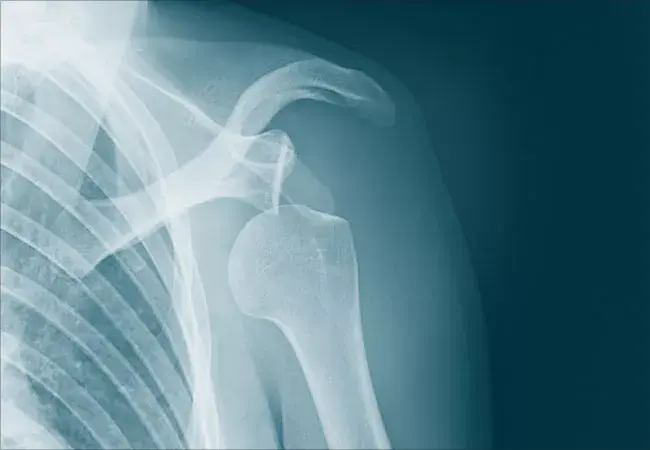

Shoulder Joint

Common Shoulder Joint Disorders

Rotator Cuff Injuries

Tears, tendinitis, and impingement are common problems affecting the tendons of the rotator cuff, a group of muscles and tendons that stabilize the shoulder